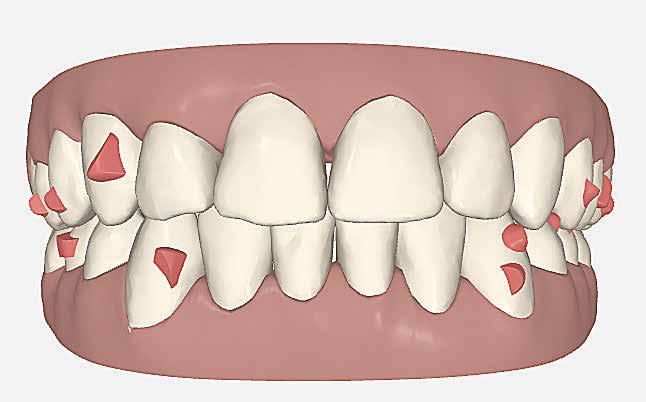

A hiányzó oldalsó kismetszők részárással történő kezelése során a szemfogak és oldalsó fogak meziális mozgatása közben a fogszabályozó orvosnak csiszolással kell a fogak formáját igazítani. Már a kezelés elejétől a szemfog elcsiszolása nem csak az incizális részre kell hogy kiterjedjen, hanem az approximális, palatinális és a vesztibuláris felszín éli negyedére is. Így érhetünk el egy rövidebb klinikai koronát, a vesztibulo-orális méret csökkenését, egy incizális élet, valamint a szemfog megfelelő pozicionálását a kismetsző helyén. A túl széles szemfog megakadályozza a megfelelő interkuszpidáció kialakítását az oldalzónában. A palatinális felszín elcsiszolásával biztosítjuk az interferenciák nélküli metszővezetést, és a megfelelő overjetet a frontfogak enyhe érintkezésével. Ha a szemfogra a későbbiekben esztétikai pótlás készül, a megfelelő approximális elcsiszolás (az esztétikai fogorvossal történő egyeztetés után) biztosítja a zenith kívánatos pozícióját a későbbi felépítéshez. A mezializált kisőrlő palatinális csücskének elcsiszolására csak akkor van szükség, ha ez akadályozza a megfelelő fogérintkezést. Az első kisőrlő mindkét csücske fontos a már a szemfog helyén álló fog esztétikai és funkcionális beállításához.

A szemfog oldalsó kismetsző helyére történő bemozgatása során a fog átalakítása javasolt a két fog eltérő morfológiai adottságai miatt (1. a-b. ábra). A fog kontúrozása, vagy úgynevezett formázása magába foglalja az approximális felszínek elcsiszolását, valamint a többi fogfelszín igazítását a kívánt fogformának megfelelően [1].

A szemfog megfelelő inklinációjának eléréséhez az oldalsó metsző helyén a palatinális felszínt is el kell csiszolni. Ennek a felületnek nem szabad interferenciát okoznia a harapásban, és lehetővé kell tennie a megfelelő metszőfog-vezetést [14]. A formázás előtt meg kell vizsgálni a szemfog vesztibulo-orális pozícióját. Lapos vesztibuláris felszínnel rendelkező szemfog esetén szükség lehet egy elsőrendű hajlításra a középső metsző és szemfog között (főleg, ha a szemfogon egy oldalsó metsző bracket van, melyben a beépített in-out érték magasabb) annak érdekében, hogy elérjük a megfelelő vesztibulo-orális pozíciót a fognyak szintjén, és elkerüljük a palatinális elcsiszolást (3. a-b ábra), [39].

Abban az esetben, ha a szemfognak kifejezettebb a központi lóbusa, a palatinális felszínről is el kell csiszolni, nem csak a vesztibuláris felszínről [40, 41]. A vesztibuláris felszín kifejezett elcsiszolása esetén ez már a dentint is érintheti, ami megnehezíti az esztétikai helyreállítást (a sárga dentin átüthet és a ragasztás is nehezebb ehhez a felülethez). Ezért a vesztibulárisan domború szemfogakat javasolt palatinálisabban pozicionálni, ami – együtt